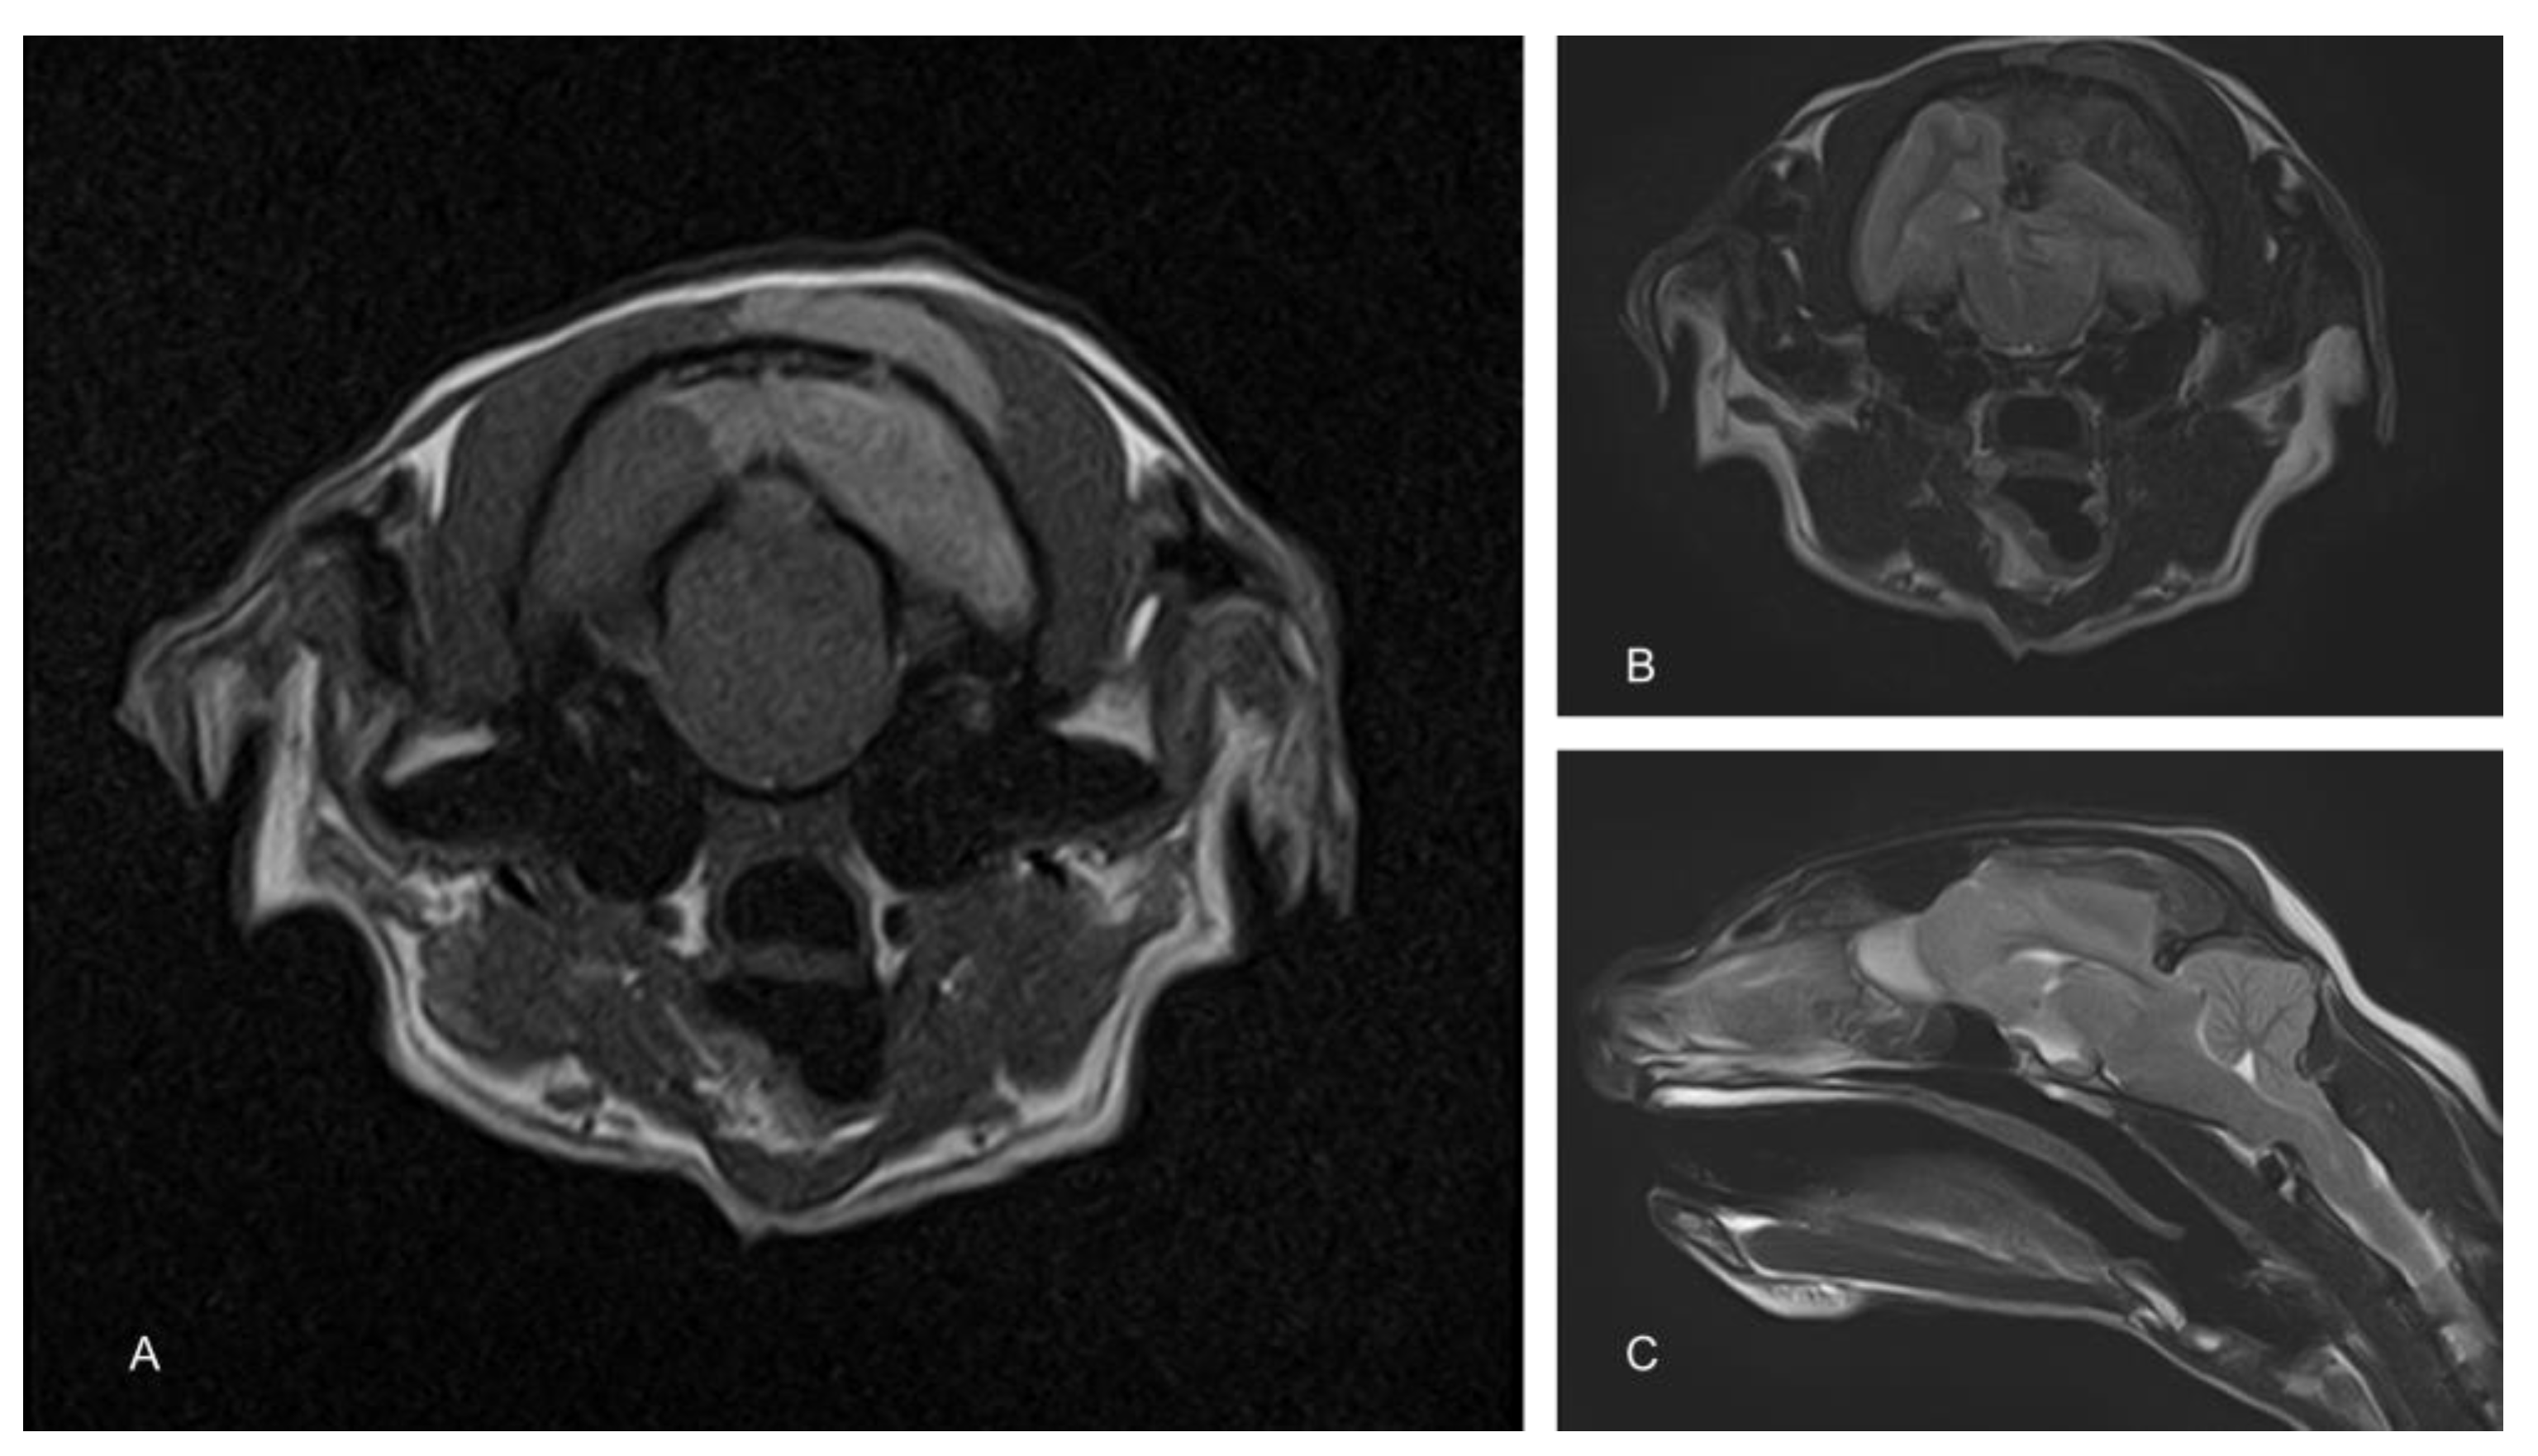

To determine the cause of the neurological signs, an MRI of the brain was performed using a 1.5T magnet (Toshiba Vantage Elan, Canon medical systems Ltd., Crawley, UK). Sequences included T2-weighted (T2W) in the sagittal (TR 5000, TE 96, 2.5 mm) and transverse (TR 8487, TE 96, 2.5 mm) planes, transverse T2W fluid attenuated inverse recovery (FLAIR; TR 11000, TE 108, 2.5 mm) and transverse T1-weighted (T1W; TR 490, TE 10, 2.5 mm) before and after the administration of contrast (Gadovist, Bayer, Ontario Canada dose of 0.1 mL/Kg = 278.2 mg gadobutrol). These showed an extra-axial space occupying a mass lesion on the left side of the cranial vault, compressing the underlying parietal and occipital lobes and causing a midline shift (Figure 1). There was also marked caudal subtentorial and foraminal herniation. The mass was hypointense on T2W and FLAIR and hyperintense on T1W images. An infiltration of similar intensity was also seen within the muscle on the extracranial side of the parietal bone.

Figure 1.

Magnetic resonance images of the cranium. The T1-weighted image shows a hyperintense extra-axial mass compressing the left cerebral hemisphere. A similar hyperintense mass is also apparent in the overlying muscle (A). T2-weighted images show a similarly positioned hypointense mass (B). Compression of the cerebrum results in significant herniation of the cerebellum through the caudal fossa (C).